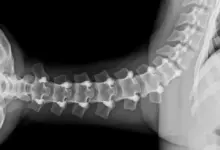

Como o médico classifica a gravidade

Dois parâmetros guiam a tomada de decisão.

- Classificação de Meyerding, que estratifica o percentual de translação.

- Análise de ângulos, como o de escorregamento e a inclinação sacral, que estimam a tendência de progressão.

Exames que confirmam

O caminho começa com história clínica e exame físico detalhados. Em seguida, os exames de imagem definem o grau e estabilidade.

- Radiografias AP e perfil, com medidas de Meyerding e dos ângulos.

- Radiografias dinâmicas em flexão e extensão, para avaliar a instabilidade.